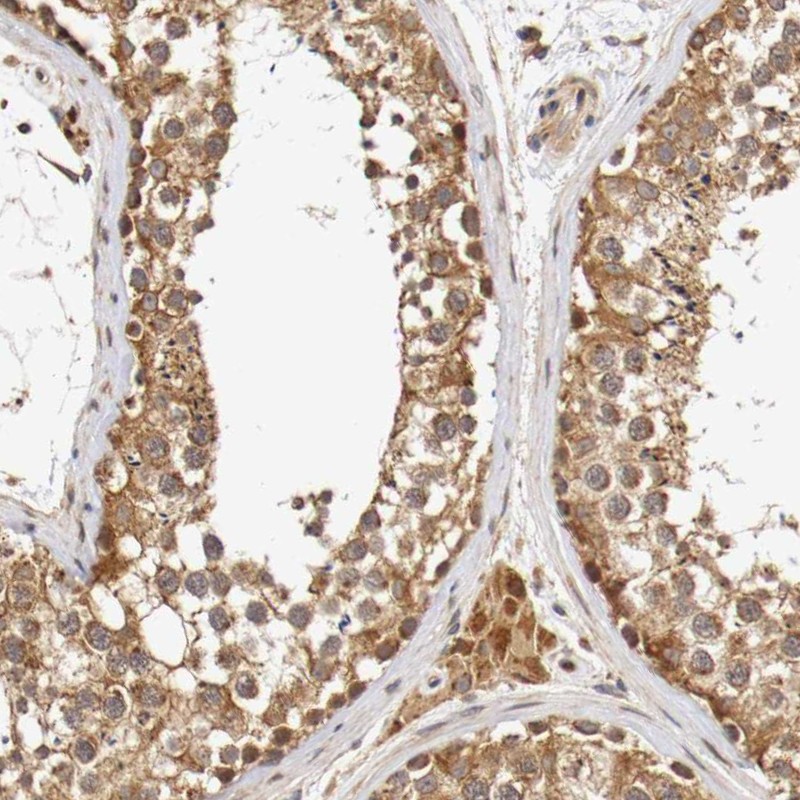

Immunohistochemical staining of human testis shows moderate cytoplasmic positivity in cells in seminiferous ducts and Leydig cells.